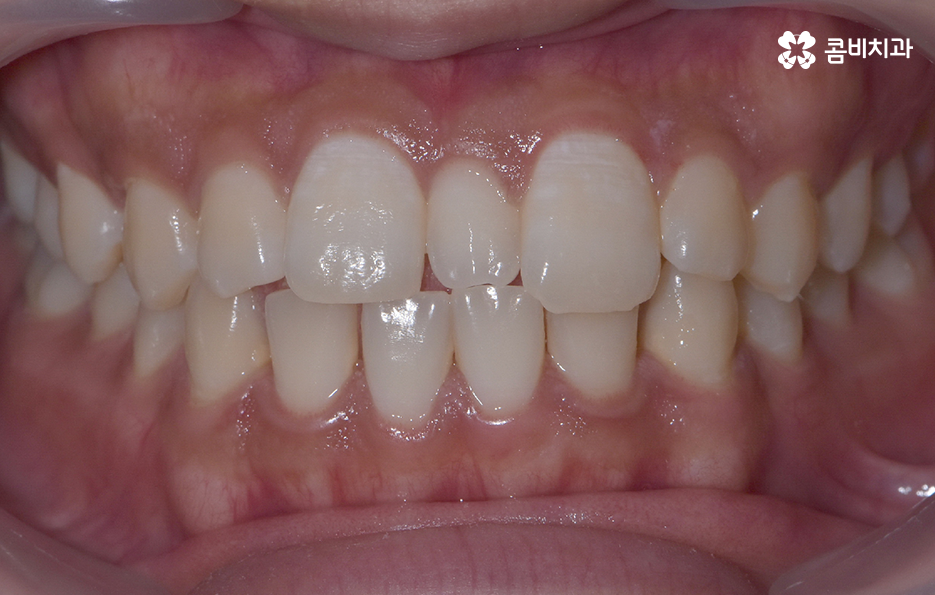

과잉치 중에서는 어떤 치아가 과잉치인지 구분이 어려울 정도로 일반적인 정상 치아의 크기와 비슷한 크기와 형태를 띄는 경우도 있는 반면에 위 사진의 케이스는 첫번째 앞니와 앞니 사이에 유독 작은 왜소치가 있는 형태이기 때문에 치아의 기능적인 문제 보다는 심미적인 개선을 필요했던 케이스로 볼 수 있어요

그나마 다행인 점은 앞니만교정을 하더라도 치아의 교합이나 골격적인 부분, 얼굴형 등에 있어서 큰 지장은 없던 경우였는데요. 물론 아랫니가 다소 벌어져 있기 때문에 전체교정을 하면 더 좋은 결과를 얻을 수 있었겠지만 환자분의 니즈에 있어서 앞니만교정을 빠르게 원했던 사례이기 때문에 앞니 부분의 과잉치 발치 후 앞니만교정을 부분적으로 진행했어요

과잉치로 인해서 치아 배열이 전체적으로 불규칙해지는 경우도 있고 돌출입의 형태로 나타는 경우도 있지만 다행이도 입술라인이나 얼굴형에 있어서 돌출은 크지 않은 상태였다는 점도 앞니만교정을 해도 어느정도 좋은 결과를 낼 수 있던 케이스로 볼 수 있어요

과잉치로 인해 말그대로 치아의 정상 범위 이상으로 치아가 배열되기 때문에 다른 치아의 배열에도 악영향을 주는 경우가 많지만 위 환자분의 케이스의 경우에는 치열 자체는 전체적으로 가지런한 편이라는 점과 특히 턱뼈가 넓은 편이라는 점에서 전체교정을 하지 않았어도 환자분이 원하는 치료의 목표는 달성할 수 있었어요